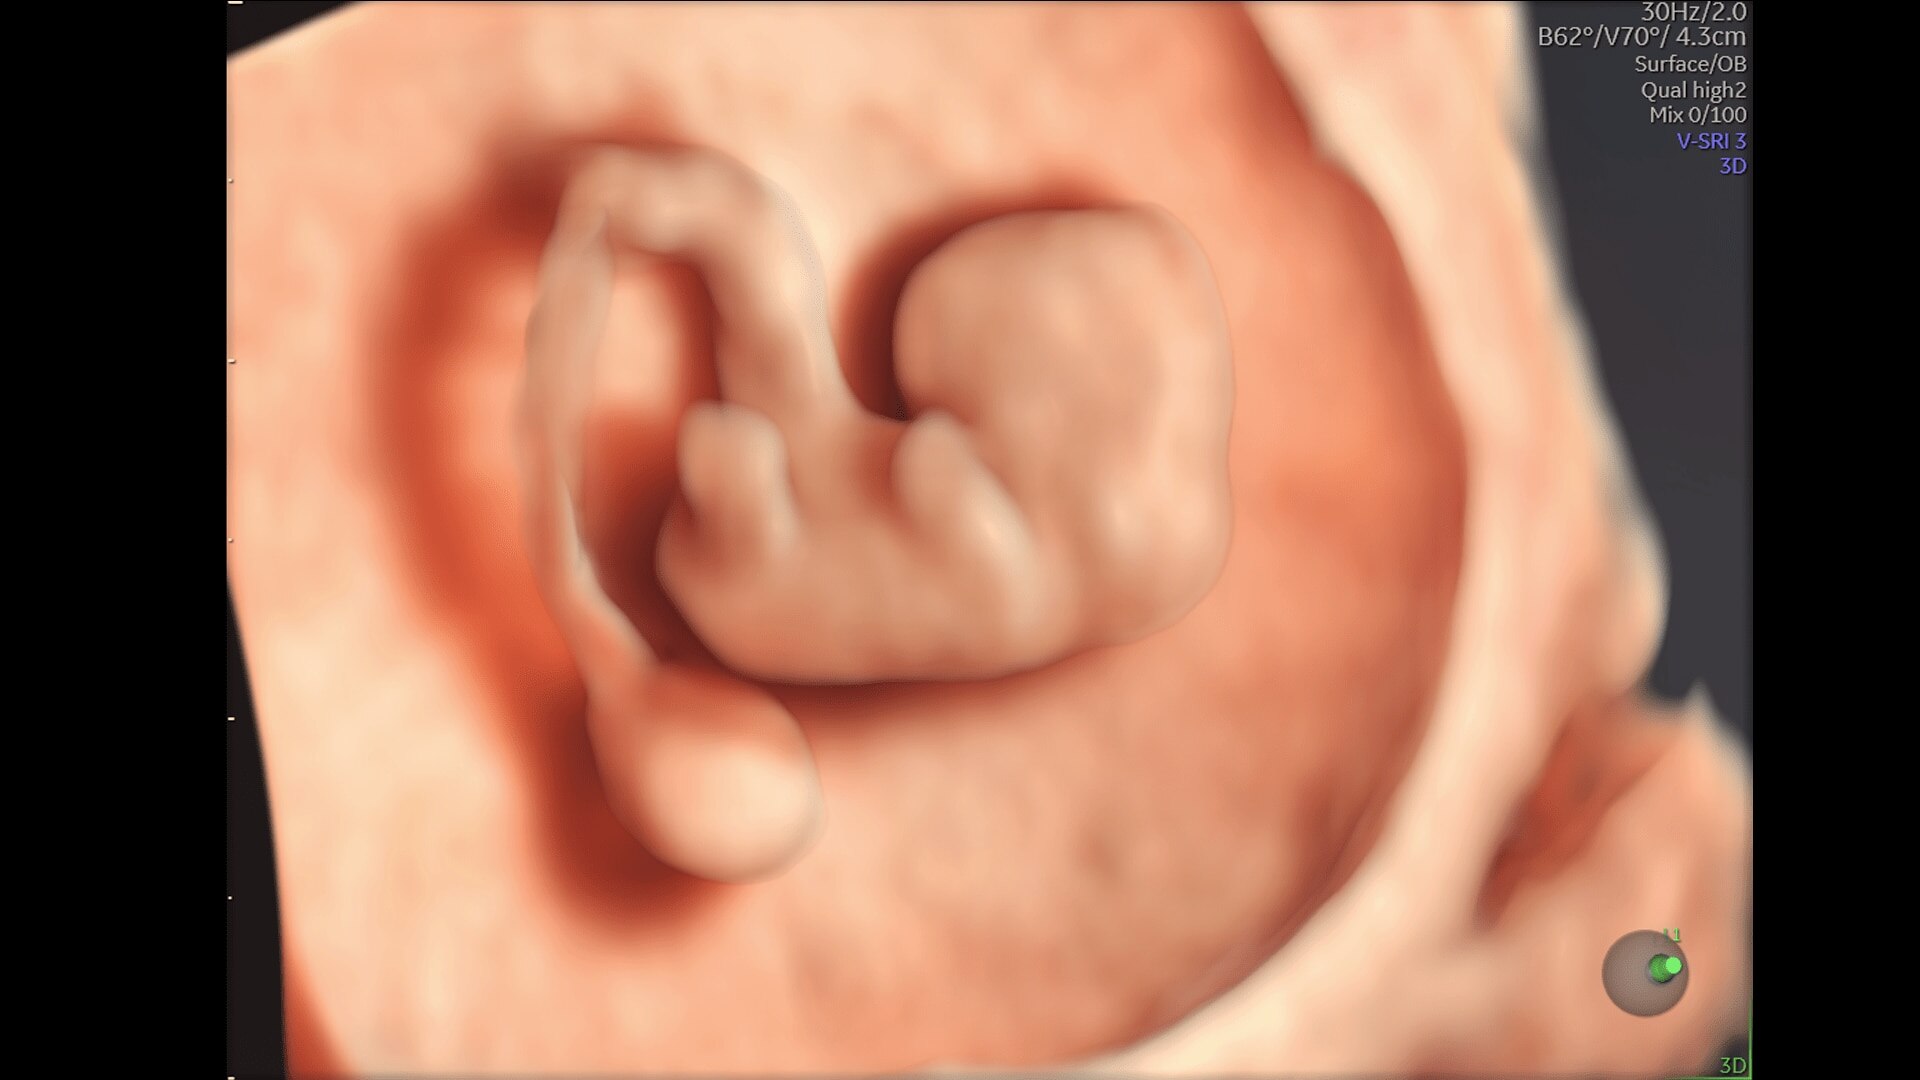

Enhanced Volume Imaging

Deliver next generation 3D/4D & Color images with HDlive Studio+